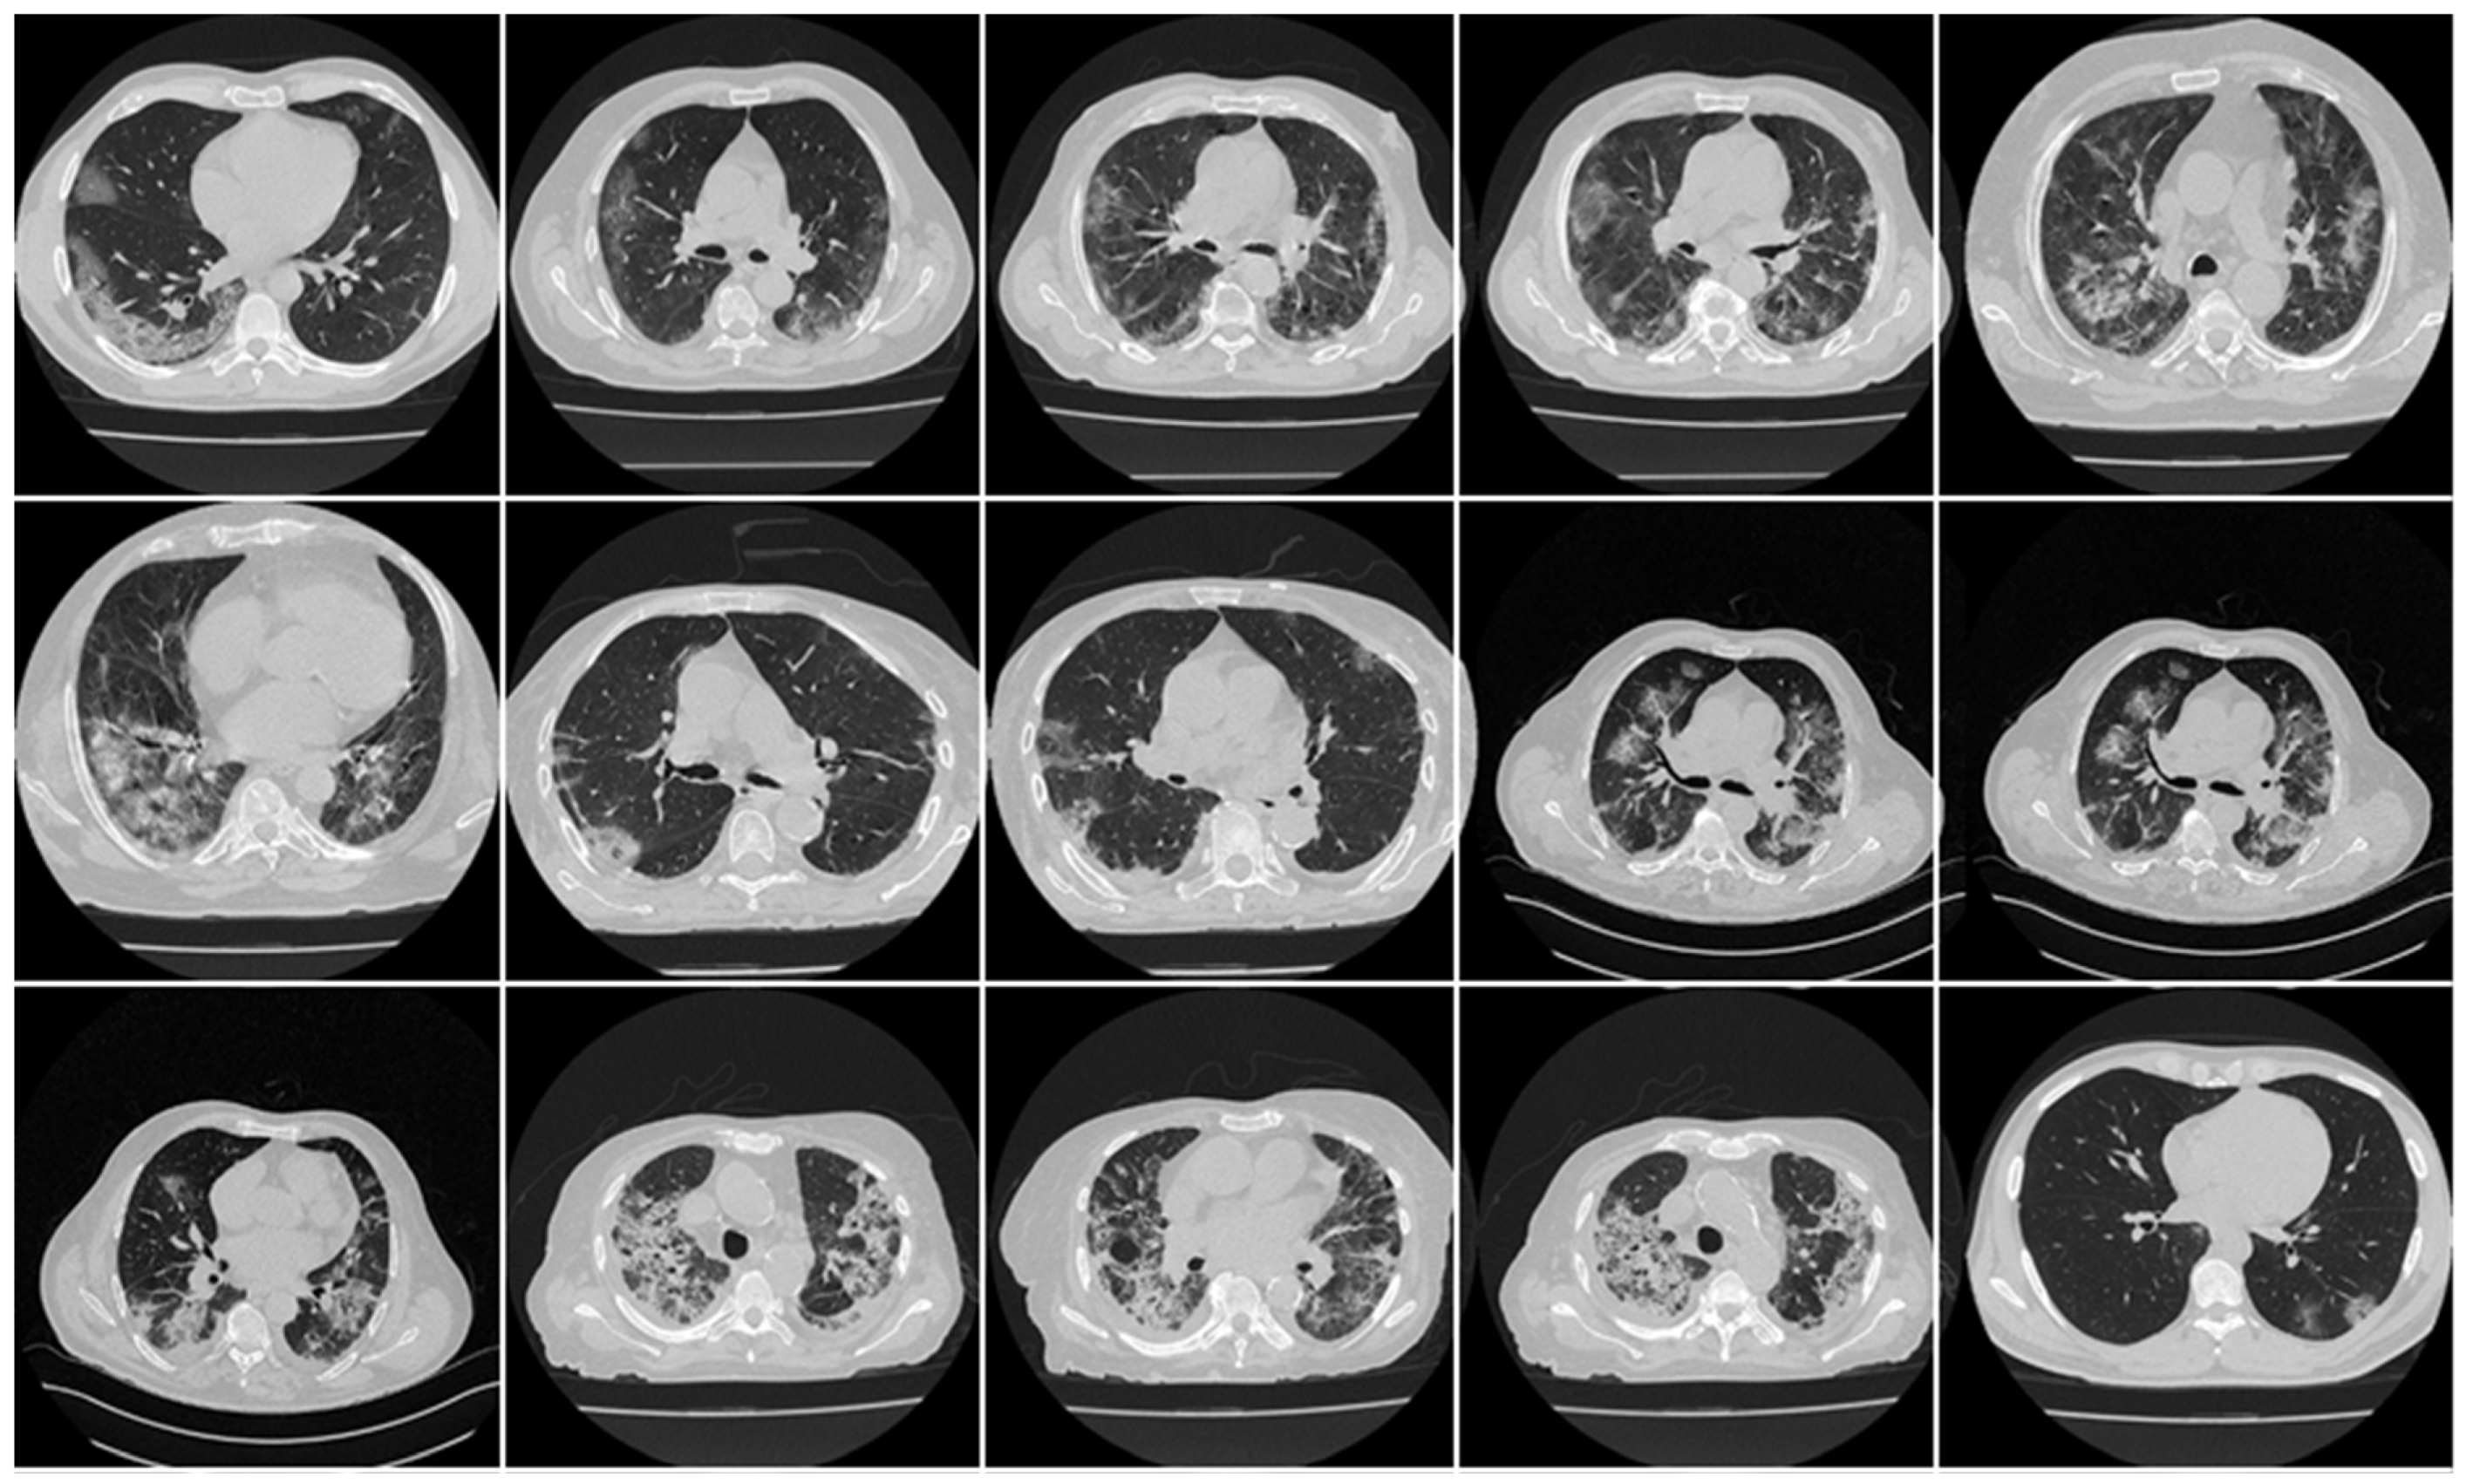

3.1. Results

3.2. Performance Evaluation